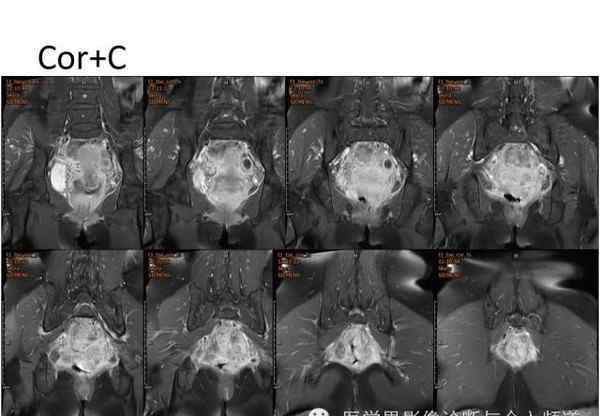

核磁共振平片扫描和增强扫描显示:

盆腔内可见弥漫性长T1长T2异常信号,FS-T2WI可见高信号,涉及直肠左前壁、直肠侧韧带和宫颈等。边界不清,盆腔可见条带状FS-T2WI高信号强度。注射钆喷酸葡胺后,病情明显加重。

腹腔镜探查:肝、胆、胃、胰、脾无异常,腹主动脉及肠系膜下动脉周围无肿大淋巴结,腹膜反射下直肠左前壁、直肠侧韧带及子宫颈坚硬,浸润成大小约5×5×4 cm的肿块,周围界限不清。